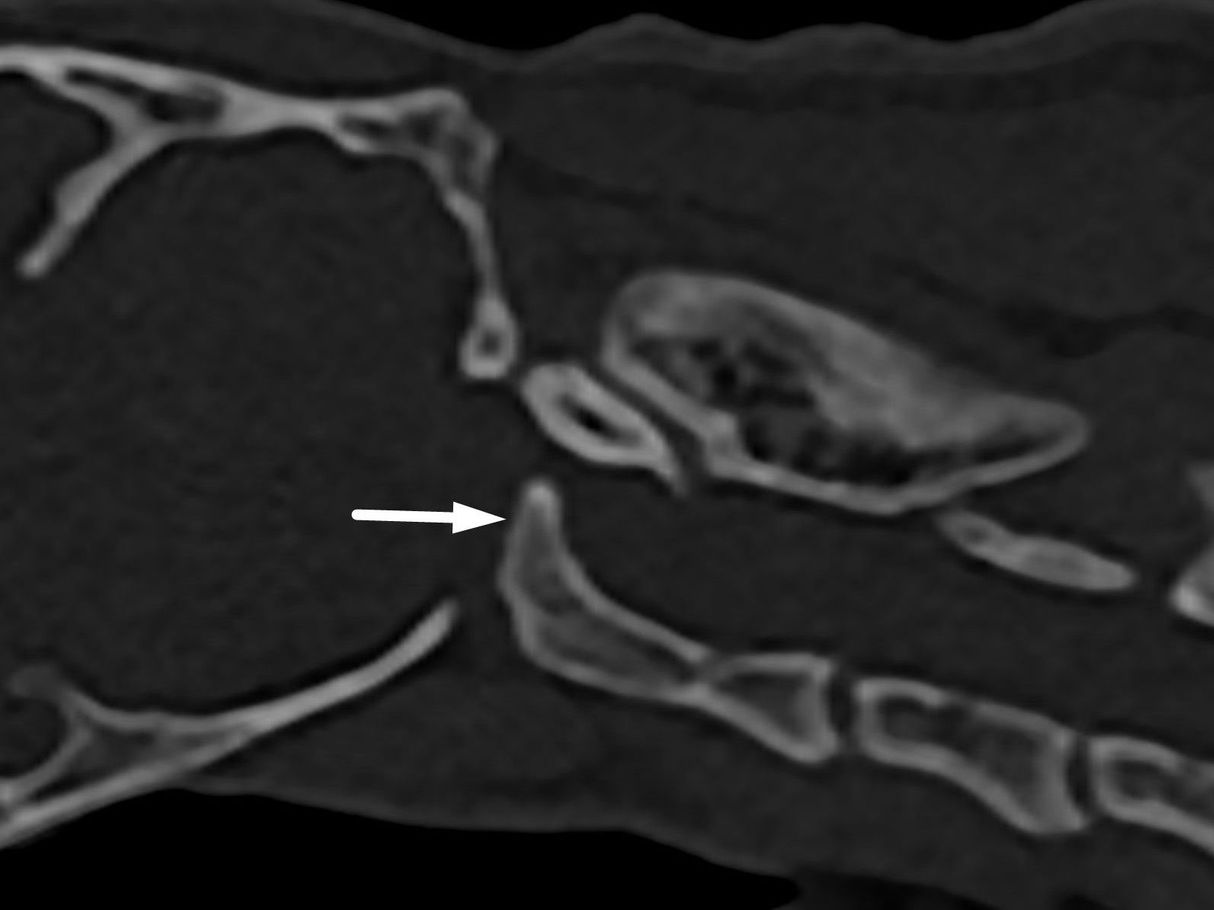

Интраренальная лоханка: рентгеновские снимки и примеры

Раздел: Фотоэссе